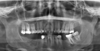

What does the red indicate in the following image?

Signmoid notch

What does the red & yellow indicate in the following image?

Red: Condylar head Yellow: Condylar neck

articular eminence

What is circled in the following image?

External auditory meatus

What is indicated by the red circles in the following image?

What does the green indicate in the following image?

Pterygopalatine fossa